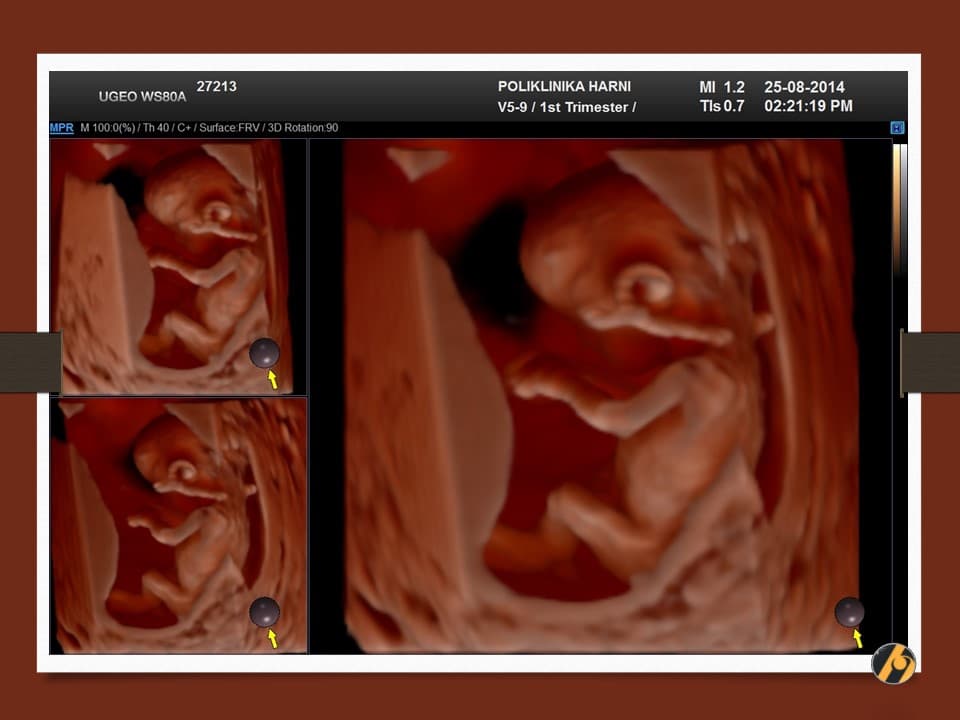

Nastavlja se oblikovanje lica koje je sve više nalik ljudskom licu. Razvitkom noktiju na rukama i nogama završava se razvitak prstića. Beba je veoma pokretna i kod ultrazvučnog pregleda se zapažaju nagli i snažni pokreti tipa trzaja - pokreti su spontanog karaktera, ali bez volje djeteta. U ovo vrijeme je kontrola pokreta djeteta još uvijek podređena živčanim središtima u leđnoj moždini, a moždani centri za koordinaciju pokreta još nisu razvijeni.

U ovome tjednu se crijeva u potpunosti smještaju u trbušnu šupljinu i ukoliko se prije vidjela omphalocoela (prisustvo crijeva u pupčanoj vrpci), sada se ta slika gubi. Formirano je i raspoznatljivo vanjsko spolovilo, koje se standardnim ultrazvučnim tehnikama još neko vrijeme neće moći raspoznati.

Vaša beba dugačka je oko 6.5 cm, a teška 10 - 15 g.